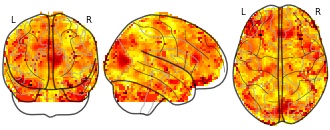

"description": "Multi-modal analysis in BPD. Brain regions exhibiting greater gray matter and enhanced activation during emotion processing in BPD compared to healthy controls. Note: Results were thresholded at p<.0025. Note2: Results were updated (see Erratum for this publication).",